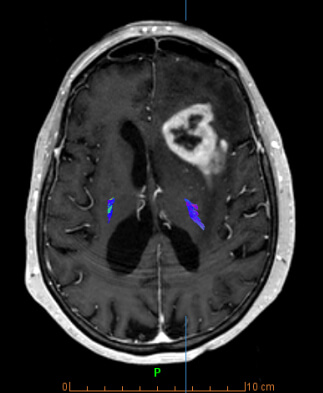

- Combination of special techniques with high-resolution anatomical images, providing additional information for tissue characterization (number of cells, blood flow and metabolic activity)

- Special Diffusion techniques (multiple b value DWI, IVIM)

- Perfusion (techniques: DSC, DCE, ASL)